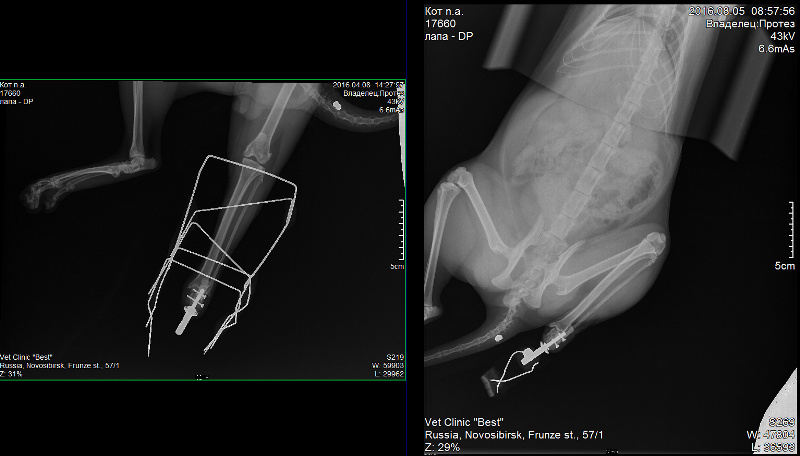

«У одного из котов отсутствовала передняя лапа, у другого — задняя. Их хозяева обратились в ветклинику, и врачи предложили им опробовать способ лечения с использованием имплантатов с нашим покрытием. Хозяева согласились, животных прооперировали. Сейчас оба они находятся под наблюдением, врачи-ветеринары систематически делают им рентген и томографию, результаты которых показывают, что имплантаты успешно прижились. Четвероногие пациенты, по словам врачей, чувствуют себя с искусственными «лапами» так же комфортно, как если бы это были их собственные», — цитирует пресс-служба Сергея Твердохлебова.

Рентгеновский снимок имплантата, сделанный через четыре месяца после операции